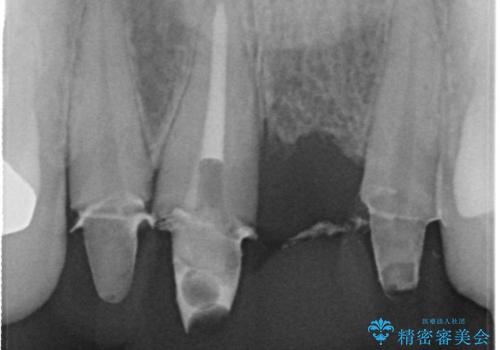

3年間仮歯 前歯セラミックブリッジ

- 3年間仮歯のまま過ごしていたそうです。 色の変色と臭いが気になり来院されました。

仮歯に変えた時点で臭いや色などが改善され、気に入っていただけました。

- 61万6千円 (根管10万x1本 コア1万x1本 仮歯1万x4本 セラミック(スタンダード)10万x4本)費用は治療当時の料金となります